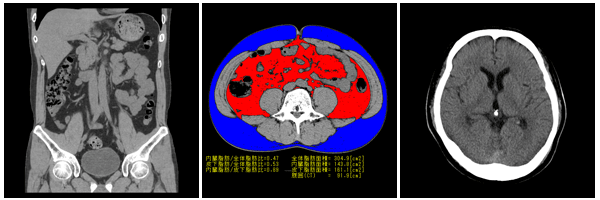

内臓脂肪からの上記の血圧上昇、血糖上昇などが問題となっておりメタボリックシンドロームとして注目されています。当院の機器では腹囲だけでなく内臓脂肪も計測可能でありきめの細かい診療が可能となっております。

1.体の周りのさまざまな方向からX線撮影したデータをコンピュータで処理して、 輪切りの画像を16枚同時に得る装置です。 2.16断面を一度に撮影し瞬時に画像が得られるため。従来のCTに比べ撮影時間を短縮し、 患者さんの負担を低減しています。 3.頭部、胸部、腹部など全身を撮影することができます。 4.撮影した輪切りの画像から、任意の角度の断面像や3次元表示画像を作ることができます。 |

内臓脂肪測定

肥満には内臓脂肪と皮下脂肪があります。

内臓脂肪が過剰になると内臓脂肪から放出される物質の分泌も異常になります。その結果血糖や血圧が高めになります。

当院のCTでは内臓脂肪の測定が可能で視覚的に可能です。